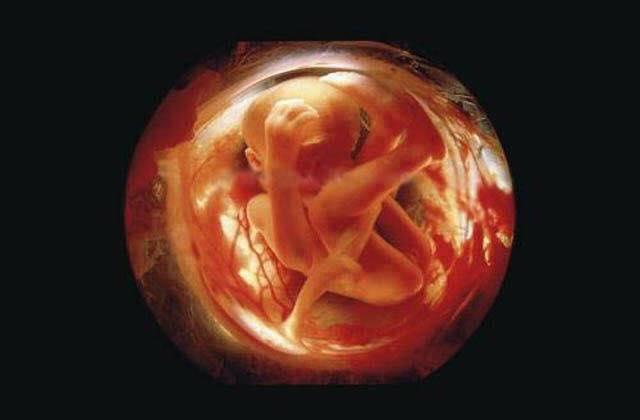

8 semanas, embrião crescendo protegido pela bolsa fetal.